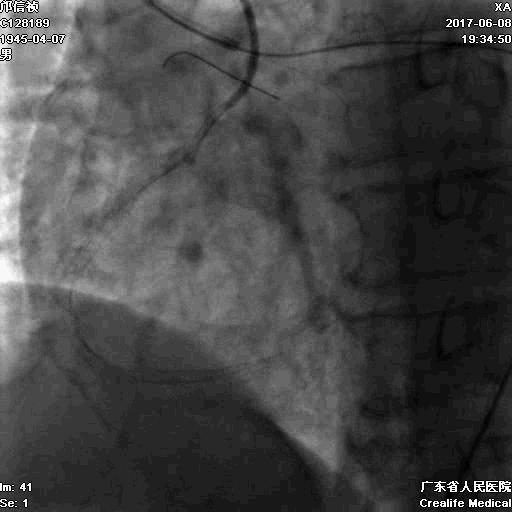

支架术后造影结果

支架术后IVUS